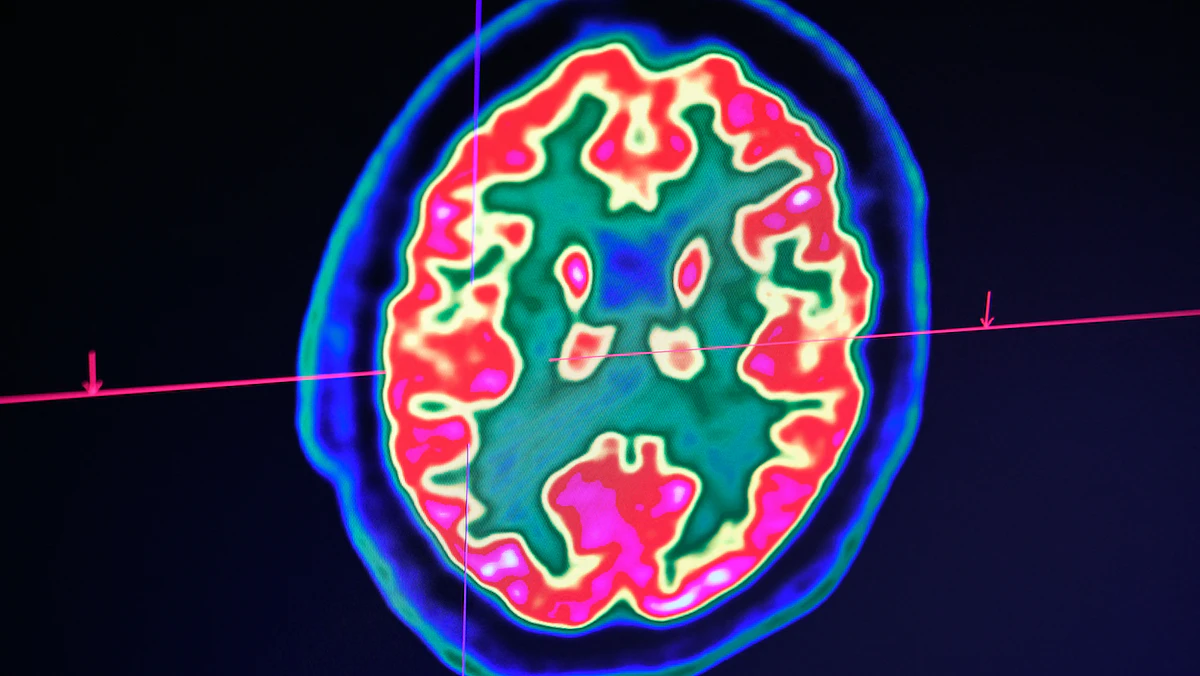

أفادت دراسة حديثة بأن العيش في المناطق ذات الخيارات الواسعة للوجبات السريعة، والتي وصفتها بـ"مستنقعات الطعام"، قد يؤدي إلى زيادة خطر الإصابة بالسكتة الدماغية بين أولئك الذين تتجاوز أعمارهم 50 عاماً.

وأشارت الدراسة التي ستُقدم في "المؤتمر الدولي للسكتة الدماغية" في الفترة ما بين 8 إلى 10 فبراير الجاري في دالاس الأميركية، إلى أن من تتجاوز أعمارهم 50 عاماً، وكانوا يسكنون قرب أماكن تقدم وجبات سريعة وبيئة غذائية غير صحية تُعرف بـ"مستنقعات الطعام"، أكثر عرضة للإصابة بالسكتة الدماغية، مقارنة بمن عاشوا في مناطق بها عدد أقل من خيارات بيع التجزئة والوجبات السريعة.